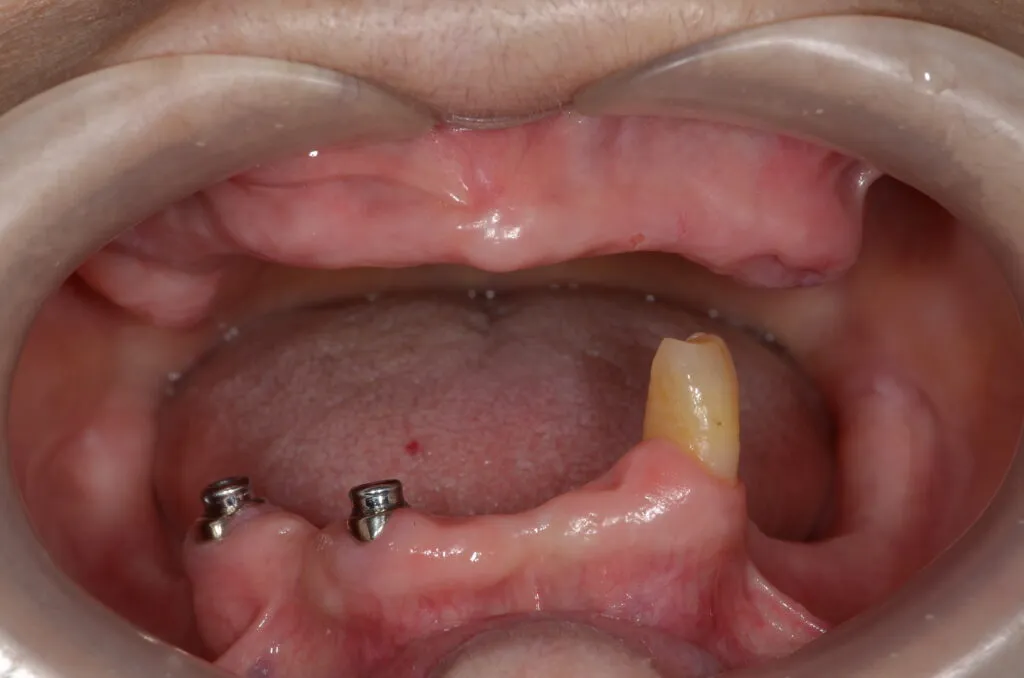

こちらの患者様の場合

【期間】2ヶ月

【費用】¥350,000~¥400,000/片顎(税抜)

【デメリット】精密に製作するため、保険の入れ歯よりも回数・費用がかかります。

上記写真は当院で上下総義歯を作製した患者さんです